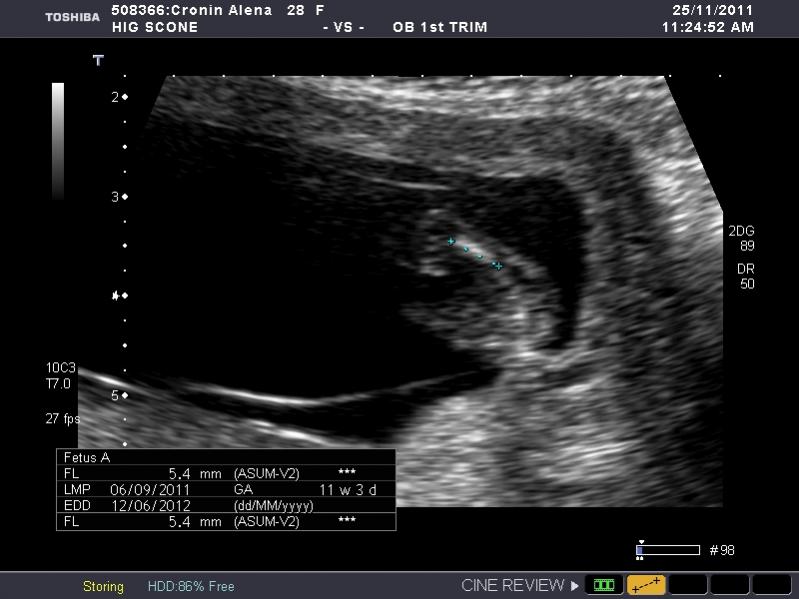

I have heaps of photos and I don't know what I am looking at so if the photo I post isn't showing anything let me know and I will try another. I am nervous as anything because I so so want a girl, but of course would still be happy with a boy. The ultrasound tech wouldn't guess.

So what is your guess.